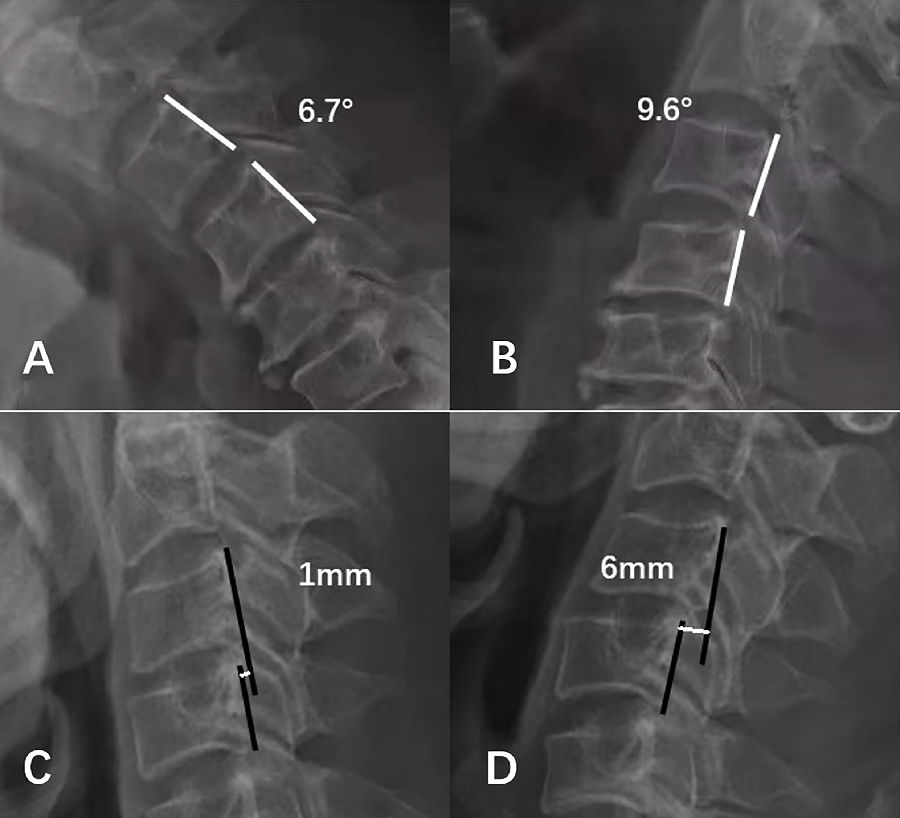

3.7 颈椎节段失稳

依据White等提出的标准,定义超过3.5mm水平位移或大于11°节段活动度为颈椎节段失稳(图5)。

图5.颈椎节段失稳示意图。A、B:角度失稳,节段活动度16.3°;C、D:位移失稳,节段位移5mm